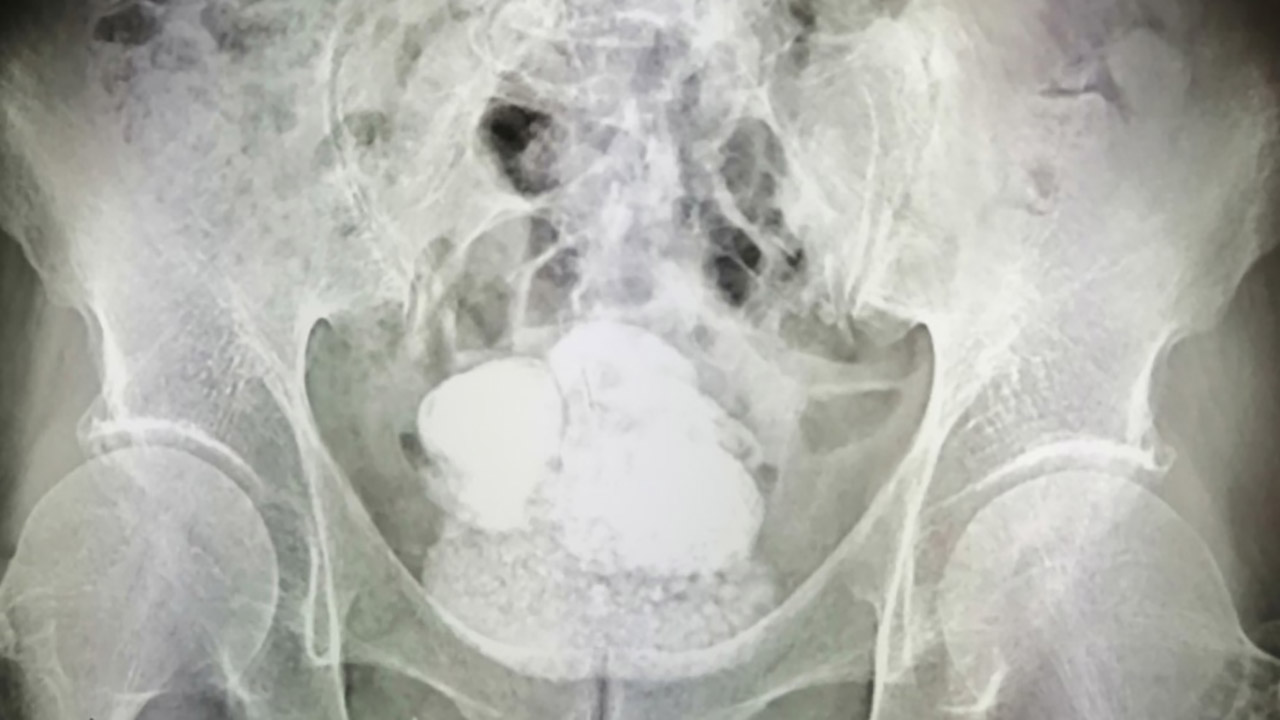

Камни на рентгене

Камни на рентгене 127 фото